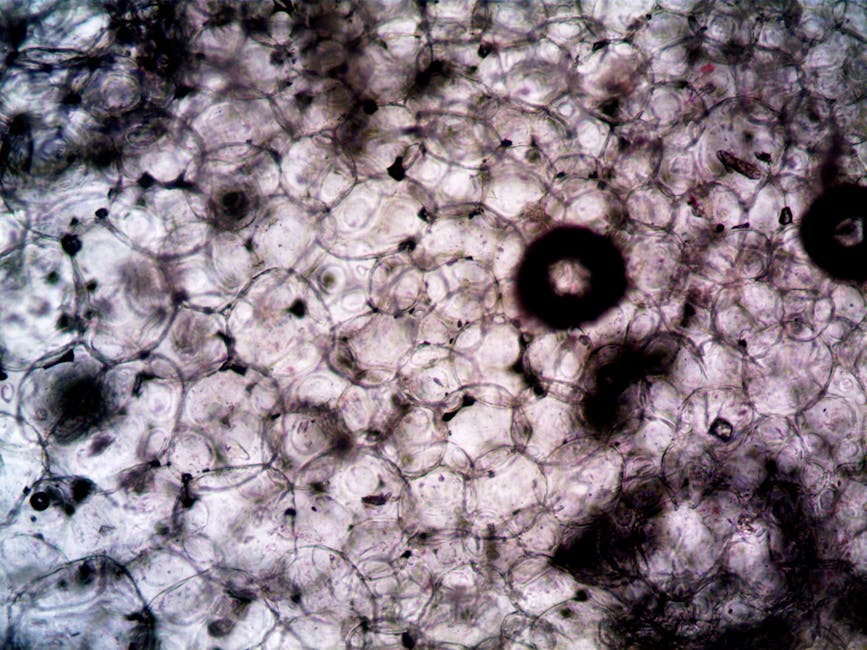

The study, which was conducted by a team of researchers at a leading university, involved the use of advanced molecular techniques to investigate the role of BAX in the aging of blood stem cells. The researchers found that when BAX was activated in these cells, it damaged their mitochondria, leading to a decline in energy production and a weakening of the immune system. Conversely, when BAX was turned off, the stem cells remained stronger and more balanced, even under stress. The study’s findings are significant not only because they shed new light on the aging process but also because they point to a potential new strategy for promoting healthy aging. The researchers used a combination of in vitro and in vivo models to investigate the effects of BAX on blood stem cells, and their results were consistent across multiple experiments.